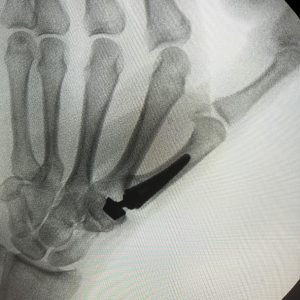

Los síntomas de la Rizartrosis incluyen el dolor en la base del pulgar al agarrar objetos o al realizar movimientos de pinza.  Muy frecuentemente el dolor se produce al abrir botes, agarrar y girar el pomo de la puerta o al girar una llave.  La fuerza de agarre y la pinza disminuye a medida que la Rizartrosis empeora y en los casos severos o avanzados la base del pulgar suele deformarse debido a la dislocación parcial o subluxación de la articulación debido al desgaste de la misma (Figura 2).

Figura 2 - Deformidad de la base del pulgar secundaria a rizartrosis.